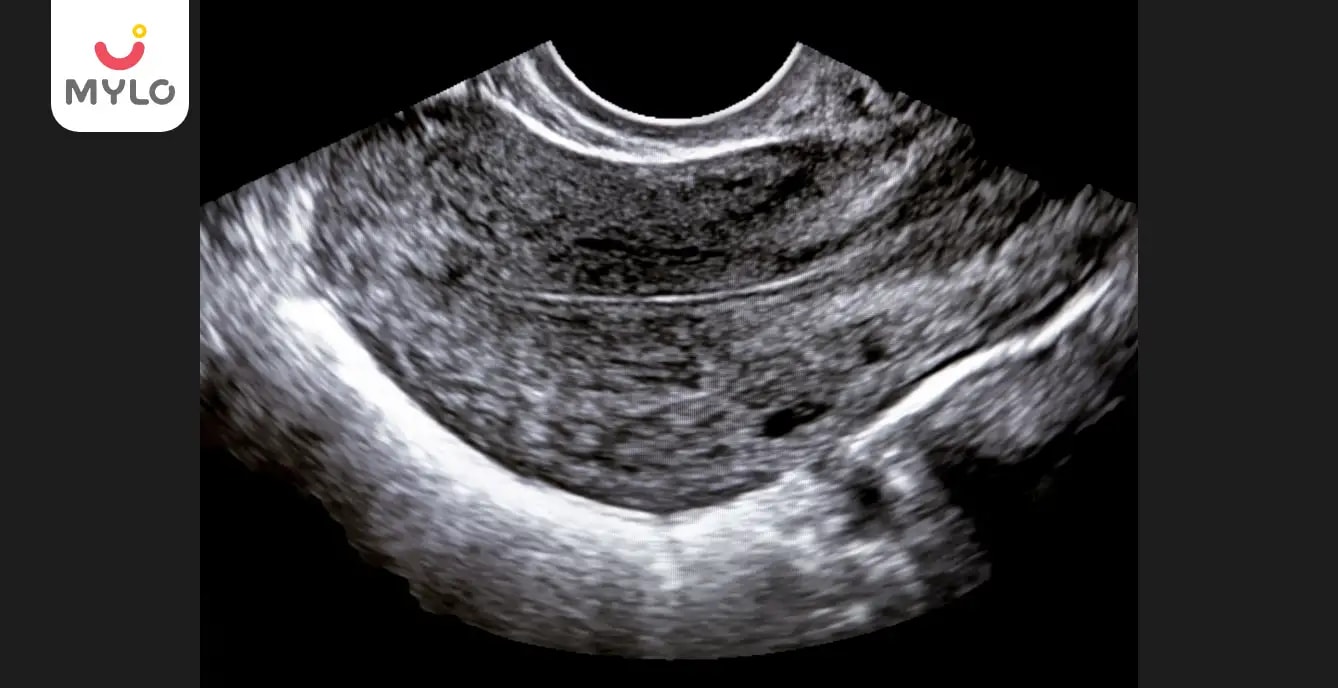

Pelvic Ultrasound Endometrial Thickness Pelvic Ultrasound

Endometrial Thickness During Pregnancy - Monitoring endometrial thickness during pregnancy provides essential insights into both maternal and fetal health. On average, an endometrium less than 14 mm thick is considered normal, regardless of menstrual phase. This is considered normal and is necessary for.